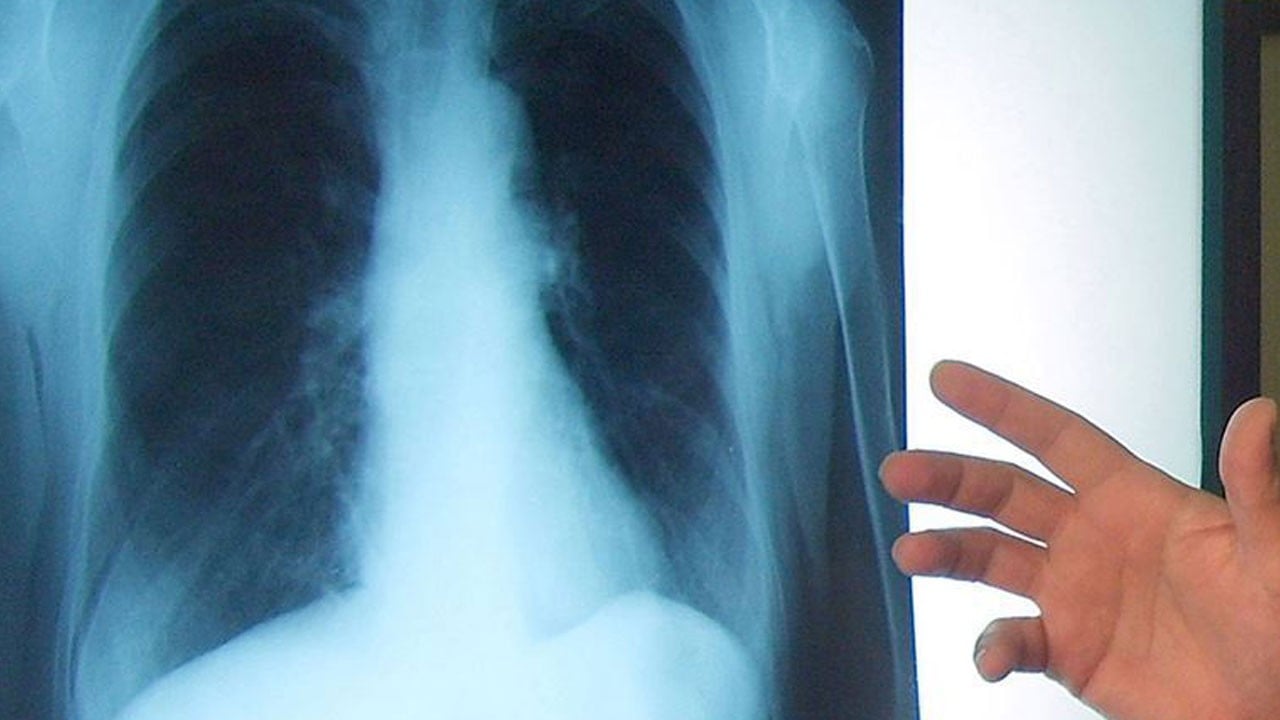

Geçmeyen öksürük, ses kısıklığı, kilo kaybı ya da nefes darlığı… Basit bir rahatsızlık gibi görünen bu belirtiler ne yazık ki akciğer kanserinin habercisi olabilir.

Geçmeyen öksürüğü önemsemedikçe tehlike büyüyor. Akciğer kanseri, çoğu zaman grip ya da bronşit zannedilen belirtilerle ortaya çıkıyor ve fark edildiğinde iş işten geçmiş olabiliyor. İzmir Şehir Hastanesi Göğüs Cerrahisi Uzmanı Prof. Dr. Figen Türk, 1-30 Kasım Akciğer Kanseri Farkındalık Ayı kapsamında değerlendirme yaparak, bu hastalıkla ilgili farkındalığın çok önemli olduğunu söyledi. Vatandaşları basit gibi görünen şikayetlerle ilgili mutlaka uzman bir hekime görünmeleri konusunda uyaran Prof. Dr. Türk, "Kimse hasta olmak istemez ama şikayet varsa da üzeri örtülmemeli. Mutlaka bir sağlık merkezine başvurulmalı. Akciğer kanseri; geçmeyen öksürük, ağızdan kan gelmesi, kilo kaybı, ses kısıklığı, nefes darlığı ve ağrı şikayetleri ile veya farklı nedenlerle tetkik edilirken tesadüfen saptanabiliyor. Aynı zamanda genetik yatkınlık, sigara kullanımı veya çevresel başka maruziyetler varsa daha dikkatli olunması gerekiyor. 'Akciğer kanserine bıçak değmez, ameliyat olmaz' gibi inanışların aksine her hastanın kendi özelinde değerlendirilip, cerrahiye uygun olan hastaların belirlendiği bir tedavi yaklaşımı doğrudur. Duruma göre açık veya kapalı ameliyat yöntemleri tercih edilmektedir" diye konuştu.